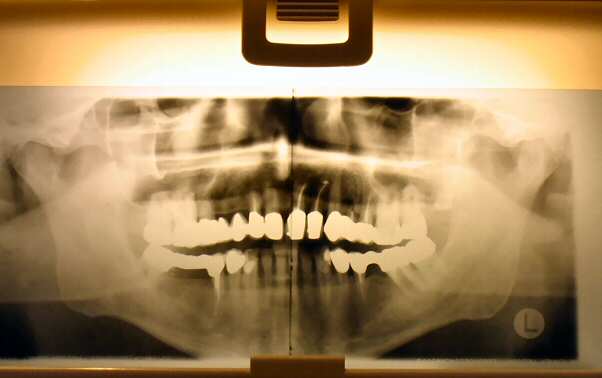

Als ich im Sommer 1980 aus Bremen nach Göttingen zurückkehrte, brauchte der Sohn der Zahnarzthelferin einen neuen Zahnarzt. Kollegen machten einen Vorschlag, und ich war sofort überzeugt, wenn auch (zunächst) aus nicht-fachlichen Gründen: "Geh mal zu Konrad, da gibt es im Wartezimmer Musik von Dire Straits". Nach 25 Jahren als Patient habe ich den Eindruck, einen guten Rat bekommen zu haben. Aber: mal abwarten, wie meine Einschätzung beim 50-jährigen Patienten-Jubi sein wird .... |